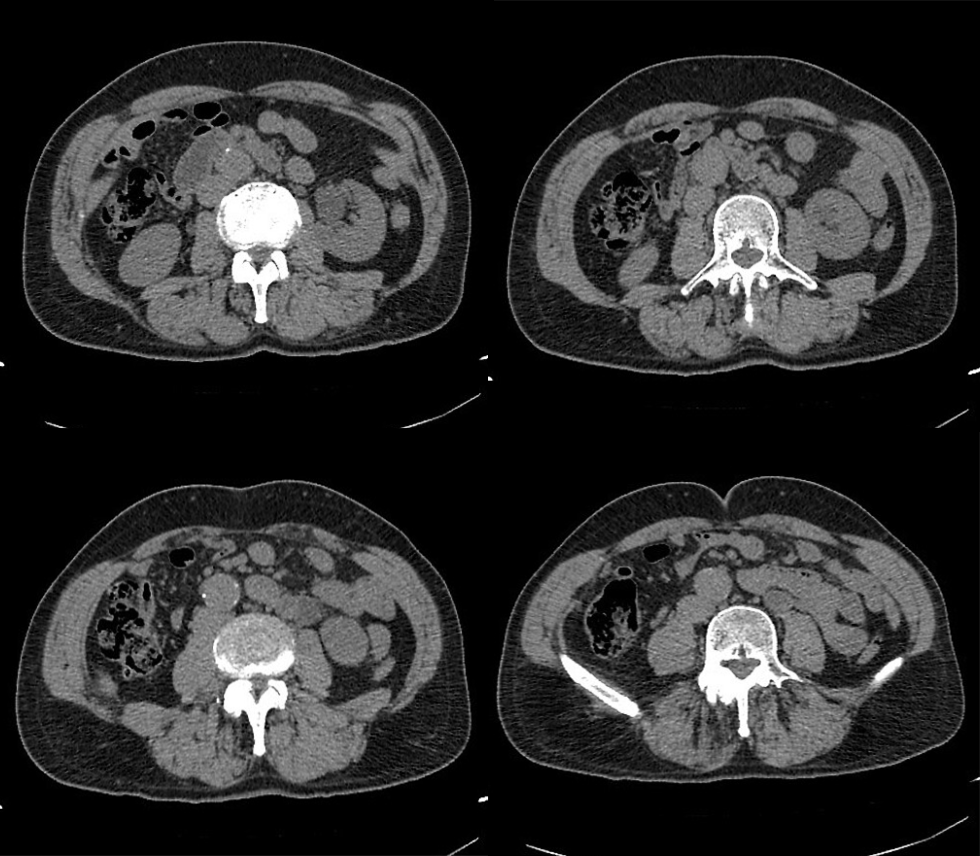

动脉期

静脉期

这不就是囊肿嘛?还有什么疑问?

笔者:你跟患者说,让他再起来到门口不要走开,等 15 分钟后再给回来扫一次,仰卧位扫一次,俯卧位扫一次;

技师:为什么啊,干啥还是俯卧位扫描?

笔者:等 15 分钟后我再告诉你,:

15 分钟后,患者再次扫描

俯卧位

笔者:你看看发现什么不一样的嘛?

技师:咦!这个囊肿和以前的囊肿不一样啊,它怎么会发生强化呢?

笔者:这真的就是囊肿嘛?